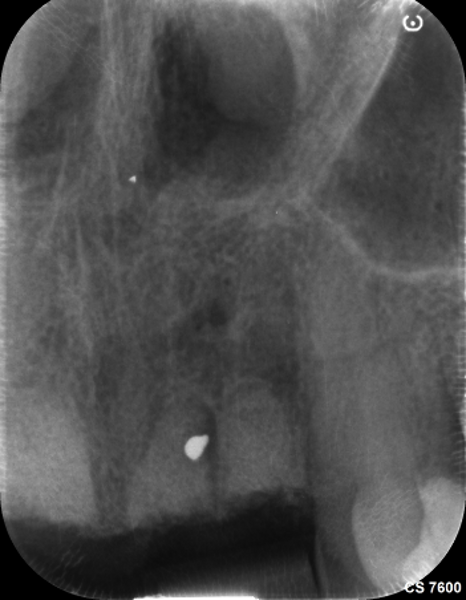

The first step was to obtain a CBCT scan of the maxillary arch, which revealed periapical pathology in teeth #12-22 (Figs. 2 & 3). Furthermore, tooth #21 exhibited significant loss of buccal bone, and a small piece of amalgam was identified in the bone near tooth #21. After a thorough analysis of the radiographic findings, a treatment plan was established to extract teeth #12-22 and perform ridge preservation to reduce bone loss in the extraction sites.

Fig. 3: Initial CBCT scan. Coronal view of tooth #21 showing buccal bone loss.